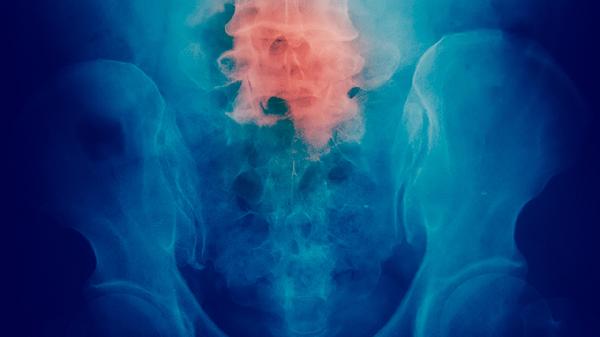

输尿管癌发生肺转移时,癌细胞通过血液循环到达肺部形成病灶,早期可能无明显症状,随着病情进展可能出现咳嗽、咯血、胸痛或呼吸困难。肺组织血供丰富且为全身血液必经之处,易成为转移靶器官,此时肿瘤负荷较大且治疗难度增加。肝转移通常表现为右上腹隐痛、黄疸或肝功能异常,肝脏作为重要代谢器官,转移灶会影响解毒功能并加速全身衰竭。骨转移多见于脊柱、骨盆和长骨,可能引发病理性骨折、高钙血症或剧烈骨痛,严重影响生活质量。远处淋巴结转移如锁骨上淋巴结肿大时,往往提示肿瘤已进入晚期阶段。

输尿管癌原发灶可通过输尿管壁直接浸润至周围脂肪组织或相邻器官,但局部浸润相对远处转移风险较低。腹膜后淋巴结转移属于区域性扩散,虽较远处转移可控性稍强,但若累及腹主动脉旁淋巴结仍属高危因素。脑转移在输尿管癌中较为罕见,一旦发生可能出现头痛、呕吐或神经功能障碍,需紧急干预。